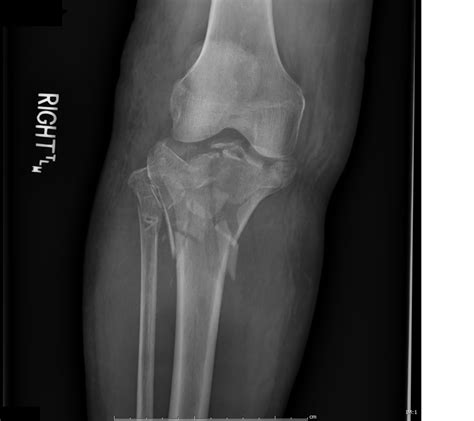

Because the tibial plateau is integral to stability, a fracture here is considered a serious injury. It not only damages the bone structure but can also affect the soft tissues, ligaments, and nerves surrounding the knee joint. Proper diagnosis using imaging techniques like X-rays or CT scans is critical to determine the severity and the best course of treatment.

Medical professionals use specialized systems to classify these injuries, which helps dictate the surgical or non-surgical approach. The Schatzker Classification is the most widely used system to categorize the fracture type, ranging from simple cracks to complex, multi-fragmentary injuries.

Classification Description

Type I Split fracture, usually lateral, without depression.

Type II Split-depression fracture of the lateral tibial plateau.

Type III Pure depression fracture of the lateral plateau.

Type IV Fracture involving the medial tibial plateau.

Type V Bicondylar fracture (both medial and lateral plateaus).

Type VI Fracture involving the plateau and the tibial shaft.